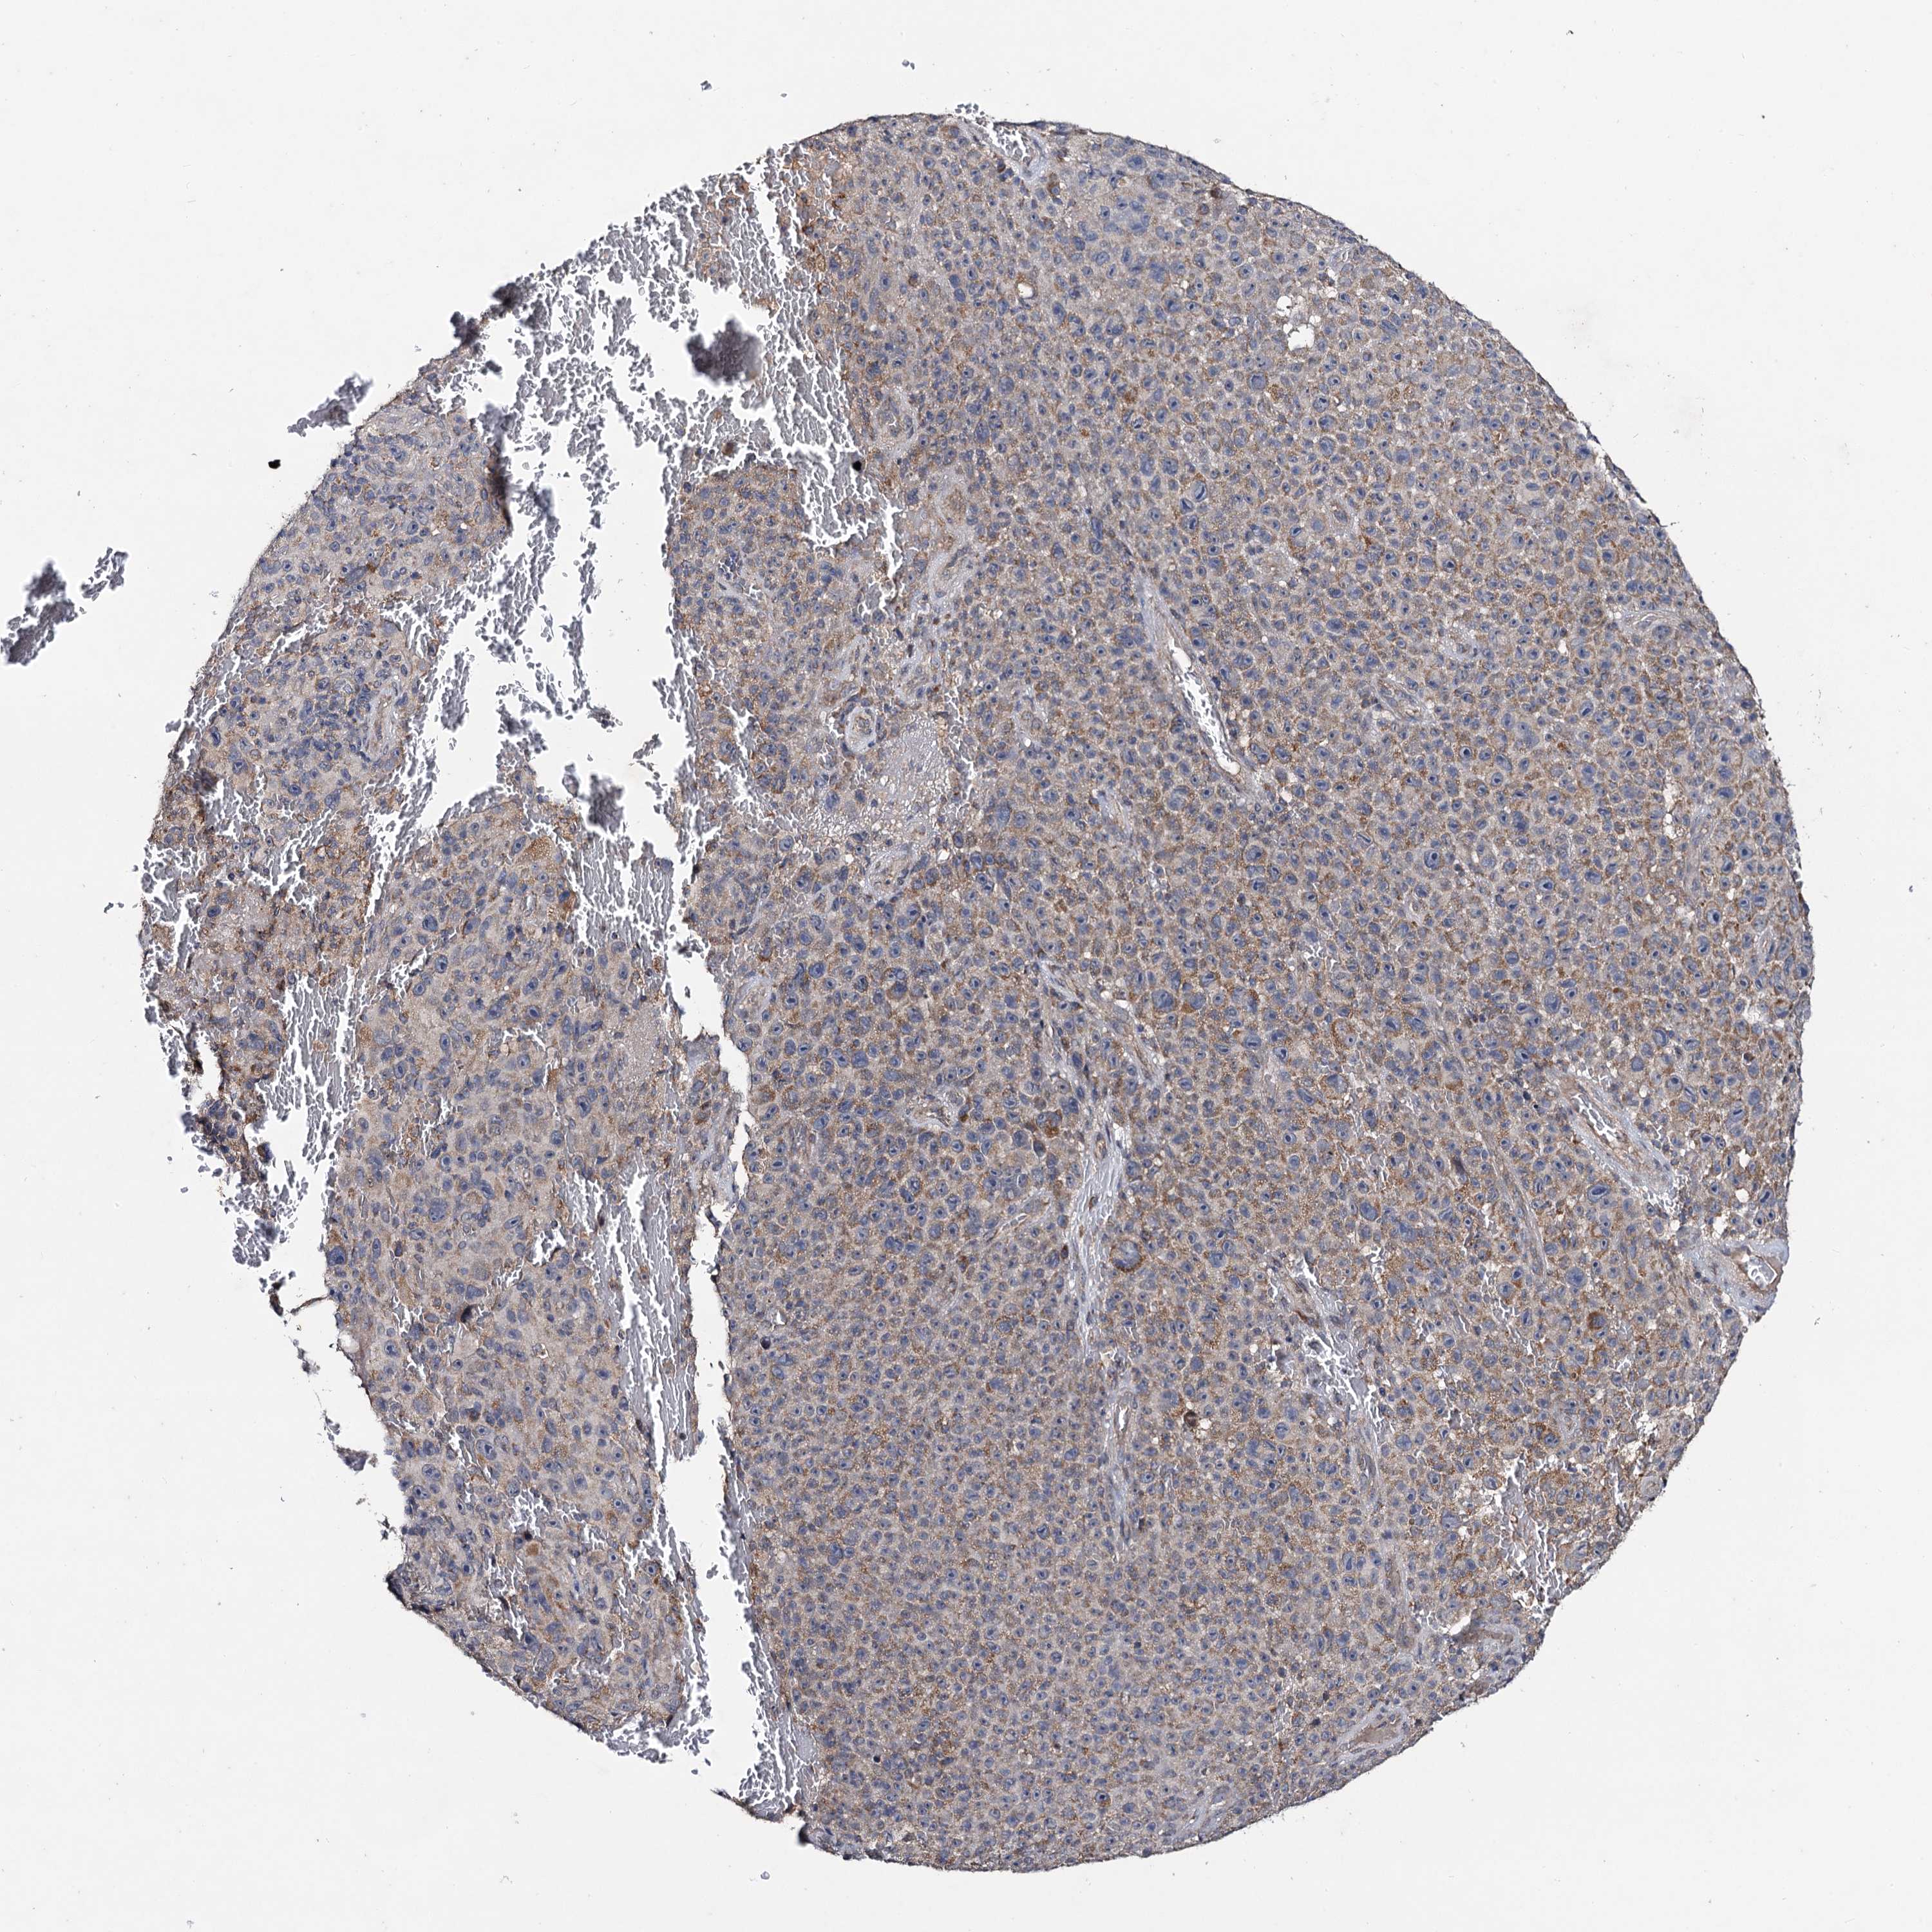

MELANOMA - Protein expressioni

A mouse-over function shows sample information and annotation data. Click on an image to view it in a full screen mode. Samples can be filtered based on level of antibody staining by selecting one or several of the following categories: high, medium, low and not detected. The assay and annotation is described here.

Note that samples used for immunohistochemistry by the Human Protein Atlas do not correspond to samples in the TCGA dataset.

Antibody stainingi

Antibody staining in the annotated cell types in the current human tissue is reported as not detected, low, medium, or high, based on conventional immunohistochemistry profiling in selected tissues. This score is based on the combination of the staining intensity and fraction of stained cells.

Each image is clickable and will lead to virtual microscopy that enables deeper exploration of all samples and also displays staining intensity scores, fraction scores and subcellular localization as well as patient and tissue information for each sample.

Antibody HPA040978

Staining

High

Medium

Low

Not detected

Intensity

Strong

Moderate

Weak

Negative

Quantity

>75%

75%-25%

<25%

None

Location

Nuclear

Cytoplasmic/membranous

Cytoplasmic/membranous,nuclear

Malignant melanoma, NOS

Malignant melanoma, Metastatic site